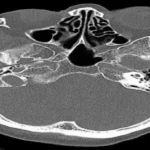

Every year thousands of children and young adults are diagnosed with life-threatening blood disorders like various types of leukemia. Leukemia or cancer of the white blood cells is a group of bone marrow diseases, where there is an uncontrolled increase in white blood cells (leukocytes). Treatment for leukemia can be complex, depending on the type.

Often, the only hope for survival is a bone marrow stem cell transplant. The chances of a sibling being a bone marrow match are 30%, while that of a non-related donor is 70%.